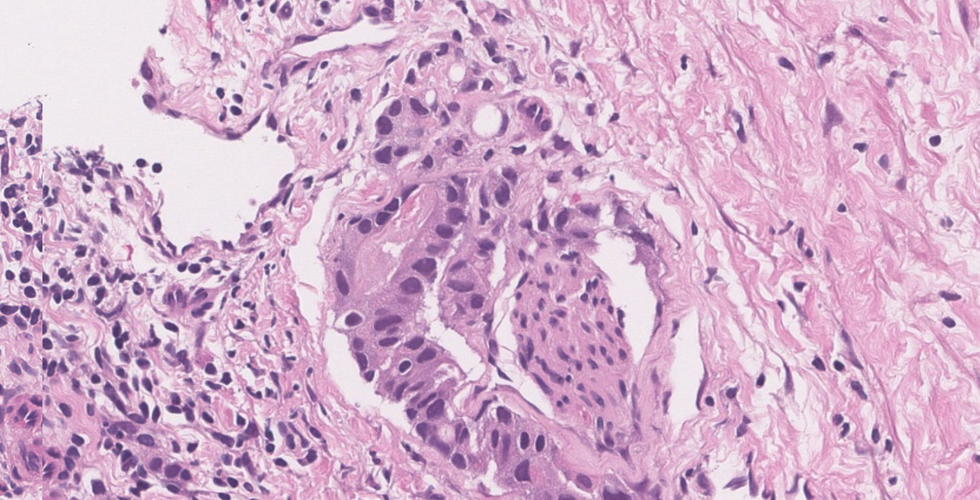

Non-Acinar Adenocarcinoma: Microscopic features

Ductal type Adenocarcinoma

● Usually involves the larger periurethral prostatic ducts (centrally located)

● Research has shown that these are more aggressive than conventional acinar type

● Can occur in pure forms or mixed with conventional acinar adenocarcinoma

● Papillary, cribriform and/or solid architecture composed of pseudostratified tall columnar cells; comedo necrosis may be seen

● Atypical large nuclei with coarse chromatin and large nucleoli seen

● Basal cells are absent (negative p63/HMWK)

● It is suggested to grade them as Gleason grade 4; if necrosis is present then they are grade 5